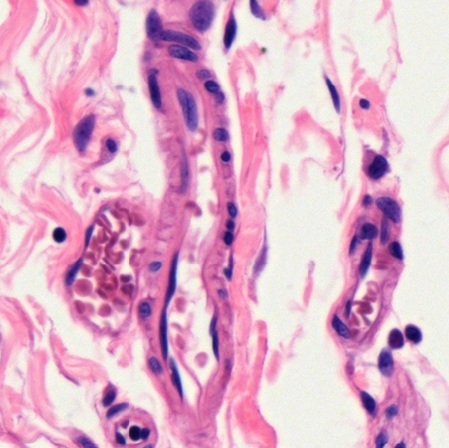

In sections of blood vessels, no matter of artery (Fig. 5-4), vein (Fig. 5-5), or capillary (Fig. 5-6), erythrocytes are found to be biconcave disc shape or dumbbell shape due to cutting. It reveals that the diameter (6-8 μm) of erythrocyte is almost the same as the thickness (7-10 μm) of a paraffin section used for light microscopic observation.